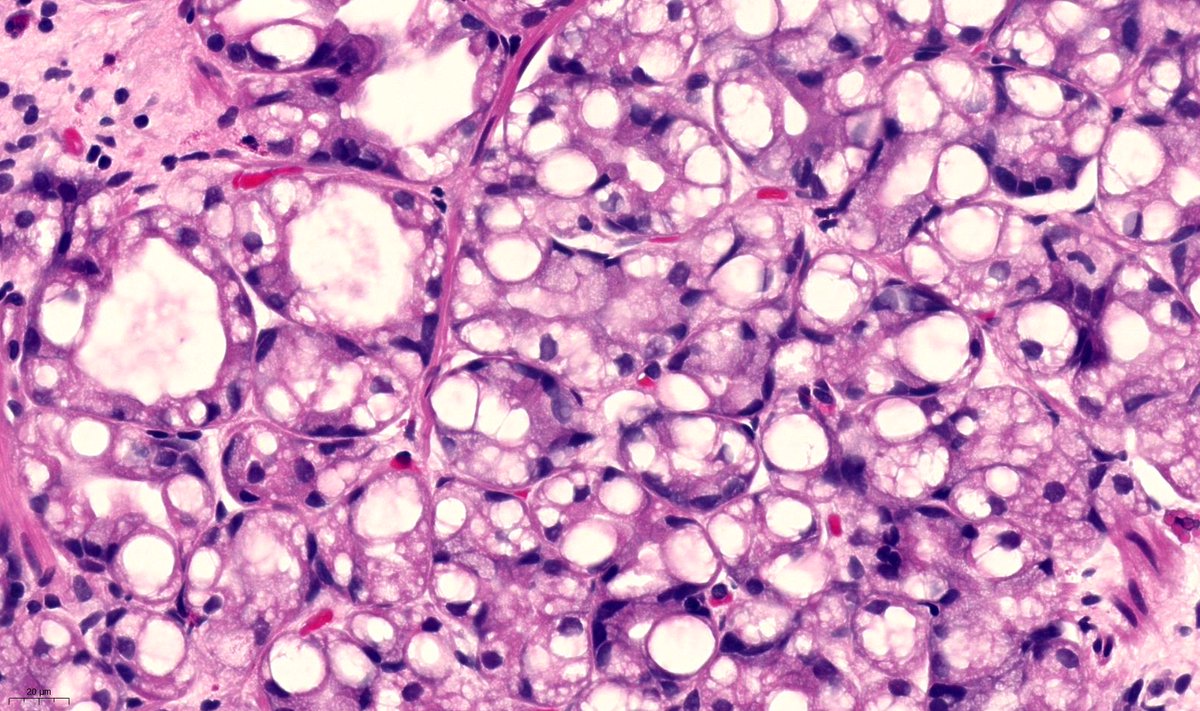

@JBennMD

Jenny Bennett, MD

5 years

Challenging on frozen section, but still one of my favorites. 54 yo F with postmenopausal bleeding and ovarian mass. 1) Diagnosis? 2) Mutation? 3) What are the vacuoles?

9

56

116